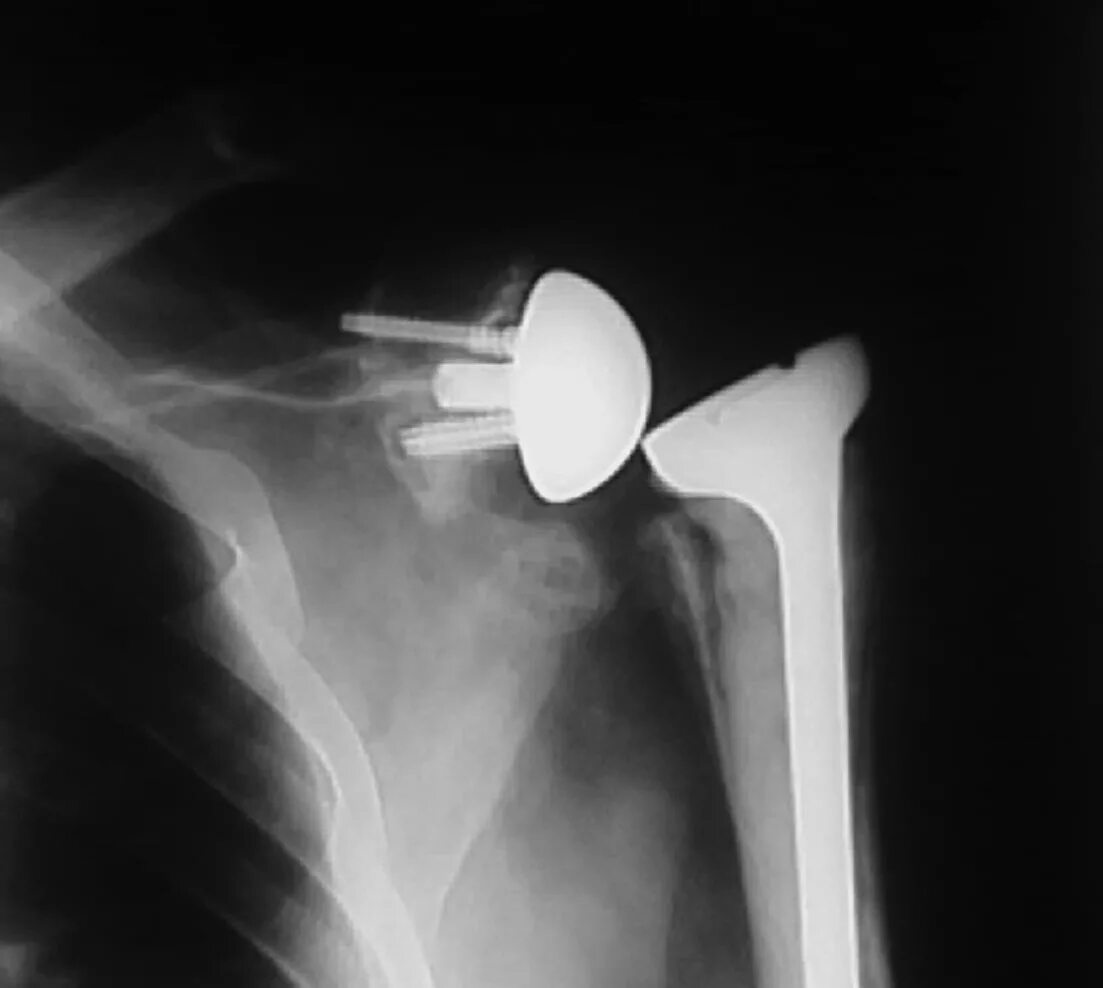

Вывих плеча у пожилых